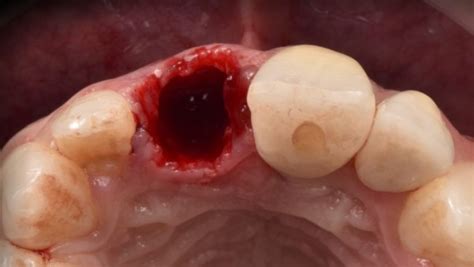

Alveolitis seca tras la extracción dental.

- Alveolitis seca: Se caracteriza por la ausencia del coágulo de sangre en el alvéolo, dejando el hueso expuesto.

El diagnóstico de la alveolitis se basa en una evaluación clínica realizada por el dentista. Esto incluye una inspección visual del alvéolo para determinar la presencia o ausencia del coágulo, la presencia de secreciones, restos de alimentos y otros signos. En algunos casos, se pueden realizar radiografías para evaluar el estado de las encías y los dientes y descartar otras afecciones.